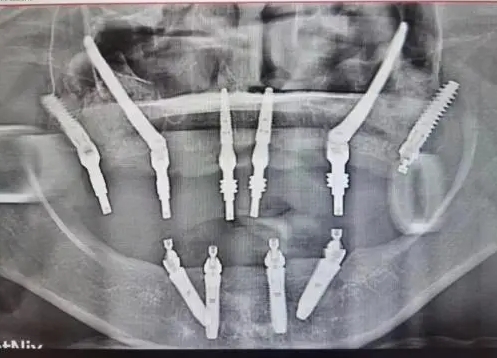

種牙在以前是個難題,不僅是技術,醫生,還有價格也是很貴的,自從有了集采,種植體的價格打下來了,便宜了,種牙的人自然也多了,接下來要考慮的就是種植牙技術了,比如VIIV技術,這也是很多人想了解的。

1、解決復雜病例:對于牙槽骨嚴重萎縮、骨量不足等疑難情況,VIIV 種牙技術能夠提供有效的解決方案,擴大了種牙的適用范圍。

2、穩定性高:通過特殊的種植體設計和植入方式,增加了種植體與骨組織的接觸面積和穩定性,提高了種植成功率。

3、減少創傷:相比傳統的復雜骨增量手術,VIIV 技術在一定程度上減少了手術創傷,降低了患者的痛苦和恢復時間。

4、即刻負重:在某些情況下,可以實現種植后即刻負重,即種植后很快就能安裝牙冠并恢復部分咀嚼功能,提高了患者的生活質量。

5、個性化治療:根據患者的具體口腔情況制定個性化的種植方案,以達到最佳的治療效果。